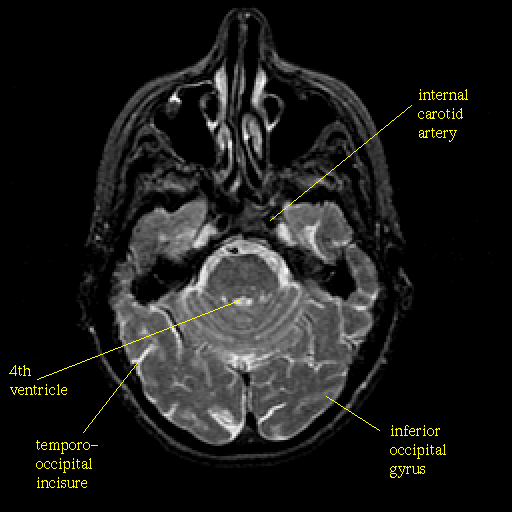

T2-weighted structural MR: Slice 16

Slice 16